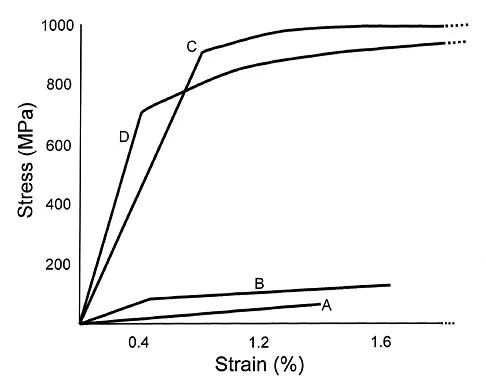

Plots of stress versus strain for four orthopaedic biomaterials are shown in Figure 3. Referring to the figure, what is the correct identification of the curves?